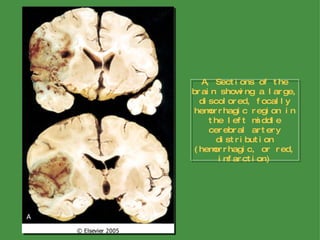

Hypoxia, Ischemia, and Infarction Infarction from Obstruction of Local Blood Supply (Focal Cerebral Ischemia) Infarcts are subdivided into two broad groups based on their macroscopic and corresponding radiologic appearance Hemorrhagic (red) infarction  is characterized by petechial hemorrhages, and is typically associated with embolic events Nonhemorrhagic (pale, bland, anemic) infarcts  are usually associated with thrombosis The clinical management of patients with these two types of infarcts differes greatly: for obvious reasons, anticoagulation may be used in cases of thrombosis but is contraindicated in hemorrhagic infarcts

A, Sections of the brain showing a large, discolored, focally hemorrhagic region in the left middle cerebral artery distribution (hemorrhagic, or red, infarction)